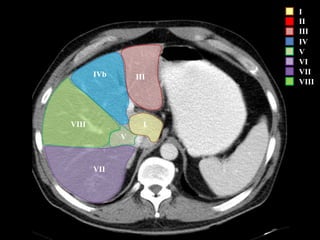

COUINAUD asignó un sistema de numeración para definir la segmentación

hepática.

IVb III

I

II

III

IV

V

VI

VII

VIII

IVb

I – Entre cava y porta

II – el más superior de los izquierdos

III – Por debajo del II

IV – por delante de la vesícula

V – por detrás de la vesícula

VI – relación con riñón derecho

VII – el más posterior de los segmentos superiores

VIII – domo hepático

Las claves de la segm. Hepática